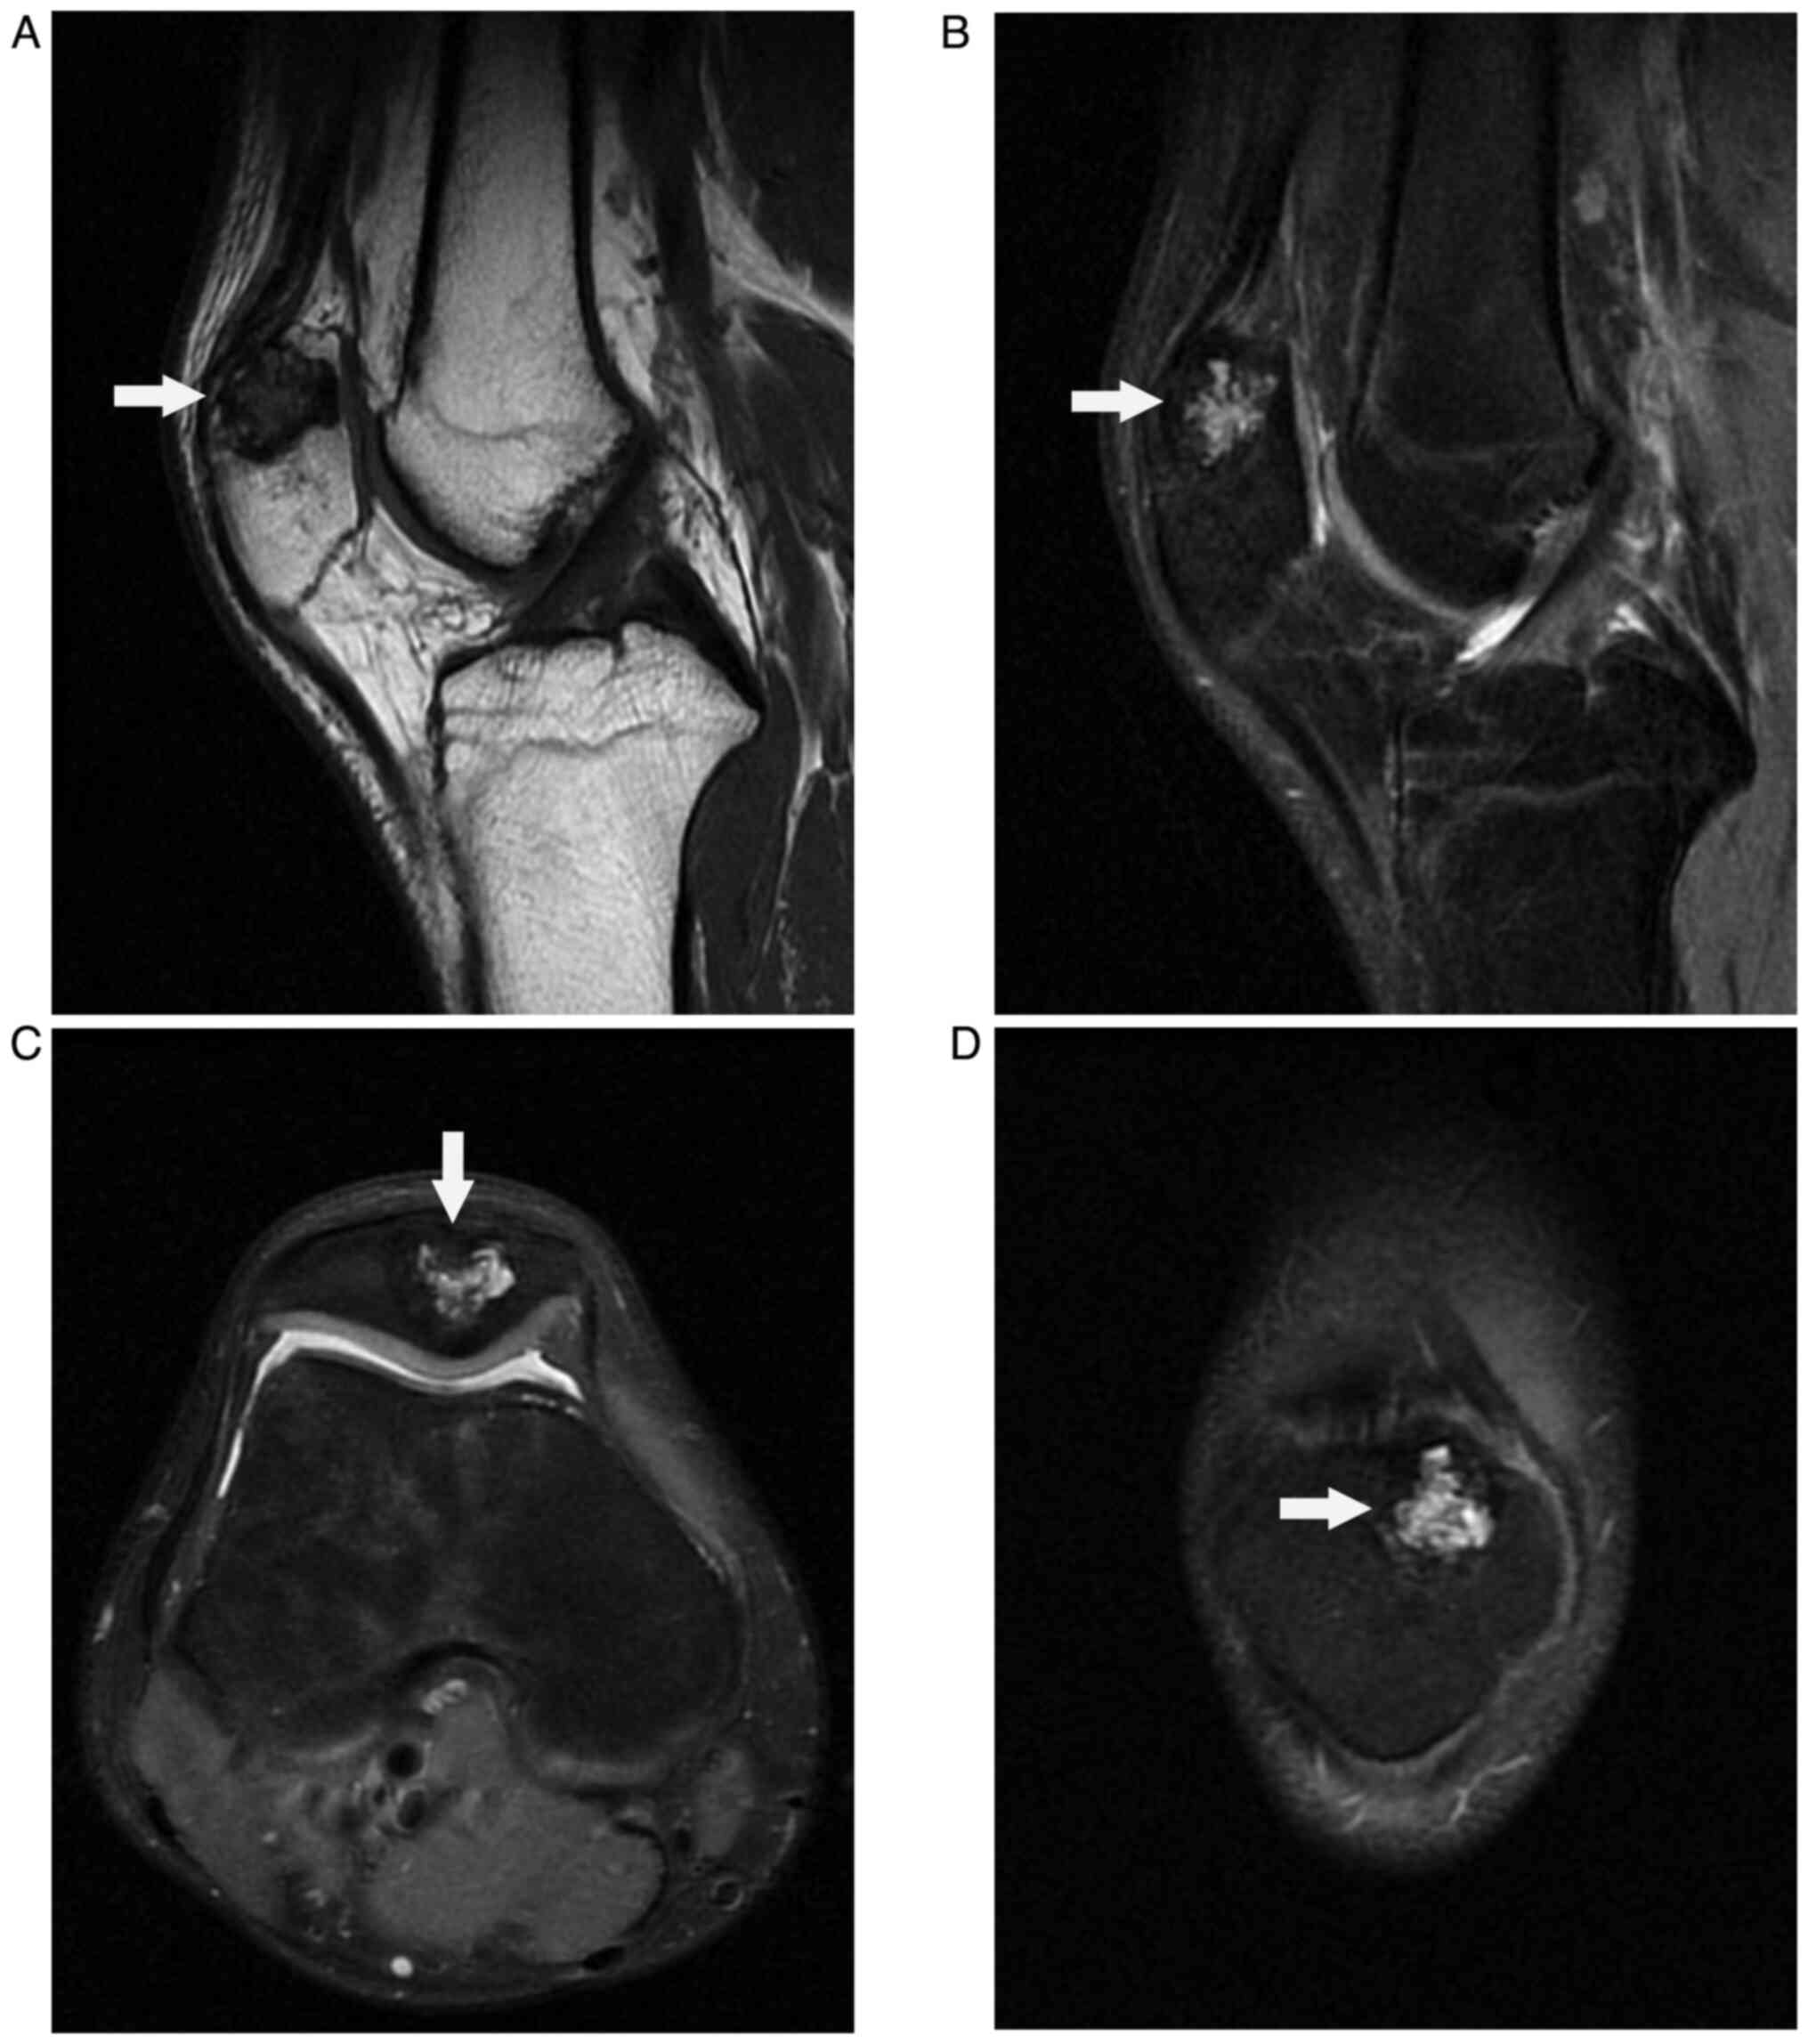

A 22-year-old male young adult was admitted to the 940th Hospital of Joint Logistics Support Force of Chinese People's Liberation Army (Lanzhou, Gansu, China) on December 5, 2020, with a 6-month history of intermittent pain in his right knee in absence of trauma. He did not have a significant personal or family medical history. His physical examination showed no obvious swelling or redness, and he had a normal skin temperature on the right knee. However, there was direct tenderness on the right patella. The range of motion of the right knee was full. The floating patella test, patella grind test, McMurray's test, anterior-posterior drawer test, and valgus-varus stress test were all negative. His neurological examination was normal. Laboratory tests revealed that his routine blood, liver function, kidney function, erythrocyte sedimentation rate, C-reactive protein, and tumor marker results were within the normal range. Radiography of the knee showed an osteolytic lesion at the medial superior quadrant of the right patella surrounded by a sclerotic margin with high density (Fig. 1). Computed tomography (CT) scan revealed a circular mixed-density image of the right patella that was surrounded by a thick sclerotic margin with high density (Fig. 2A). Three-dimensional CT showed no pathological fracture or cortical bone breakthrough (Fig. 2B and C). Magnetic resonance imaging (MRI) displayed a low-intensity signal mass on T1-weighted image (Fig. 3A) and high-intensity signal mass on T2-weighted image (Fig. 3B, C and D) with a well-defined lesion of the patella. Considering the clinical and imaging manifestations of the patient, benign bone lesions including chondroblastoma, osteoid osteoma, osteoblastoma, and bone abscess, were considered as the initial diagnosis.

Figure 3

Magnetic resonance imaging showing a low-intensity signal mass on the T1-weighted image and a high-intensity signal mass on the T2-weighted image with a well-defined lesion of the patella. (A) Sagittal plane of the T1-weighted image. (B) Sagittal plane of the T2-weighted image. (C) Axial plane of the T2-weighted image. (D) Coronal plane of the T2-weighted image.

The imaging manifestations of osteoblastoma differ depending on its location, and the results lack specificity. The most frequent X-ray manifestations of the osteoblastoma of the patella are that of an osteolytic lesion, with or without matrix mineralization and pathological fracture of the patella, surrounded by a high-density sclerotic margin with no evidence of extra-articular invasion (7,15). Aggressive spinal osteoblastoma can break through the bony cortex and invade the spinal canal and paravertebral soft tissue (16,17). CT scans are superior to MRI in showing calcification of osteoblastoma and thus are used to further confirm a well-defined lesion with fine calcifications. However, the radiological characteristics of CT are atypical. Tang P et al reported a case of osteoblastoma of the rib that was misdiagnosed as lymphomatous by CT and was confirmed by pathological examination (18). MRI helps in evaluating bone marrow edema and soft tissue component or extension of the tumor; however, there is no significant specificity to this finding.